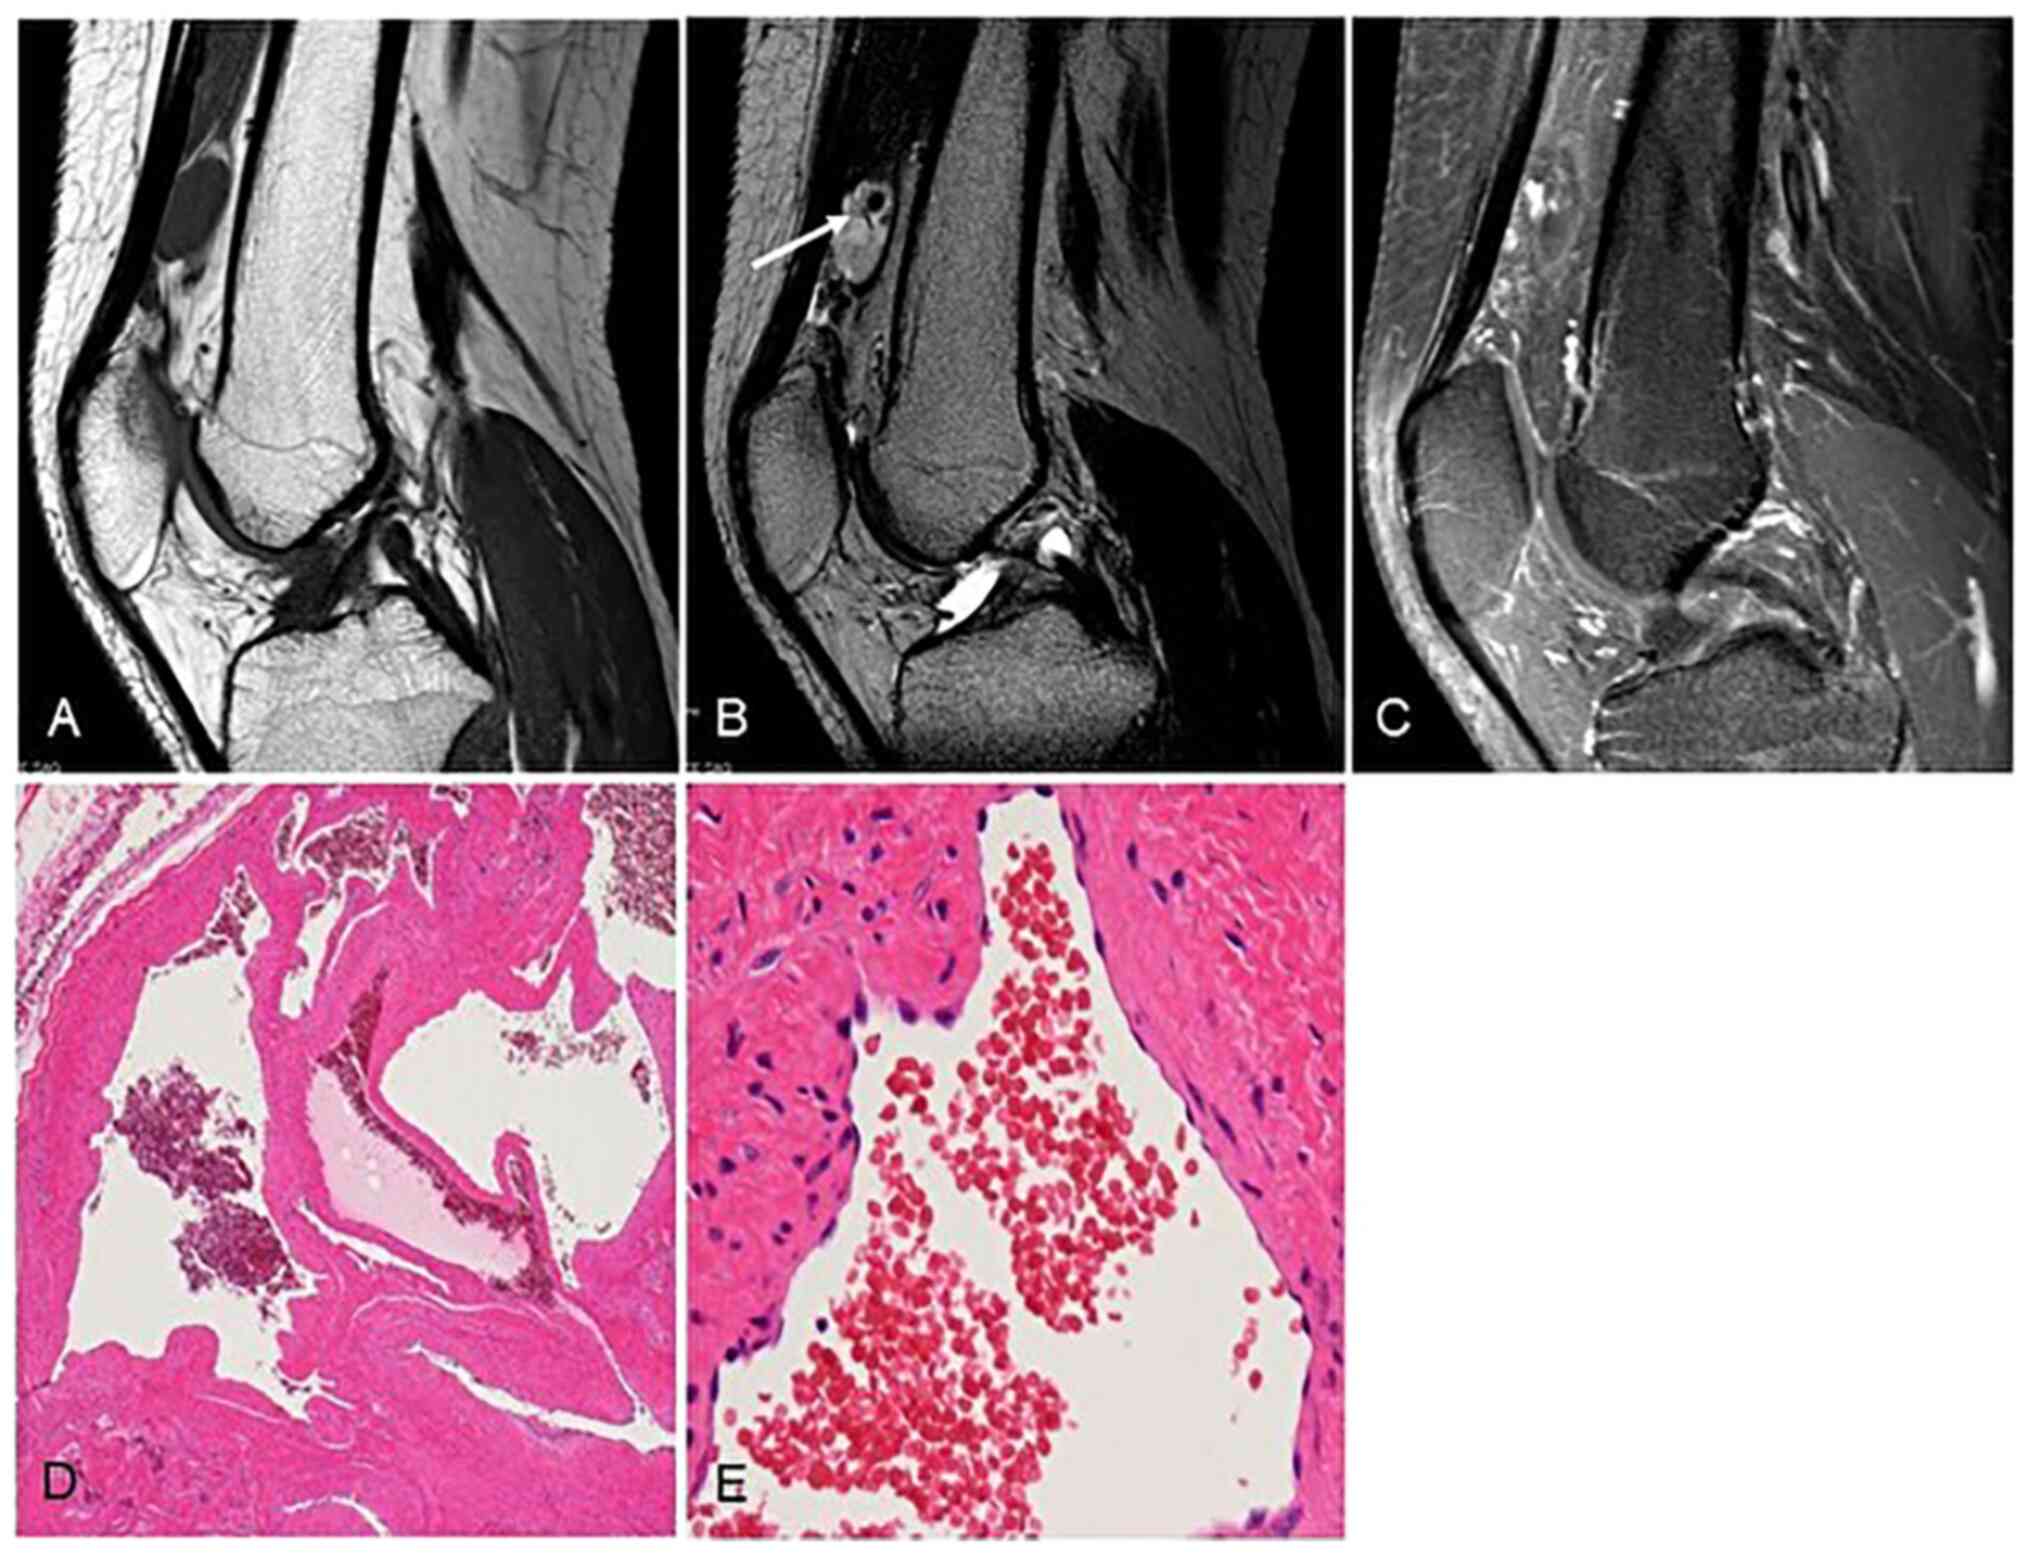

Figure 3

Representative case (patient #3, a 14-year-old boy). (A) Intra-articular calcification consistent with phlebolith (arrow). (B) Magnetic resonance imaging demonstrating a mass with high signal intensity containing a small signal void on T2-weighted images (sagittal plane). (C) Intraoperative gross findings revealing a dark red tumor covered by the synovium on the surface of lateral condyle of the femur. (D) Microscopic findings of the surgical specimen showing expanded blood lumens lacking vascular smooth muscle (high-power field, magnification x200). (E) Formation of thromboses and phleboliths caused by slow blood flow was easily identified (arrows) (low-power field, magnification x20).

Representative case (Patient #3)

A 14-year-old boy presented with a 1-month history of continuous left knee pain. Plain radiographs of his left knee joint showed an intra-articular calcification consistent with phlebolith (Fig. 3A). MRI revealed a mass with high signal intensity containing a small signal void on T2-WI (sagittal plane) (Fig. 3B). From the radiological findings, we initially diagnosed a synovial hemangioma of the knee. Since the patient's left knee pain did not improve, we decided to perform the surgical resection 9 months after the initial visit. Because of the size of the tumor, open resection was selected. Intraoperative gross findings showed a dark red tumor covered by the synovium on the surface of lateral condyle of the femur (Fig. 3C), and the tumor was completely resected. The microscopic findings of the surgical specimen showed expanded blood lumens lacking vascular smooth muscle (Fig. 3D). The formation of thromboses and phleboliths caused by slow blood flow was easily identified (Fig. 3E). The tumor was diagnosed as a cavernous SH. At 1 month after the operation, the patient's symptom had completely resolved.